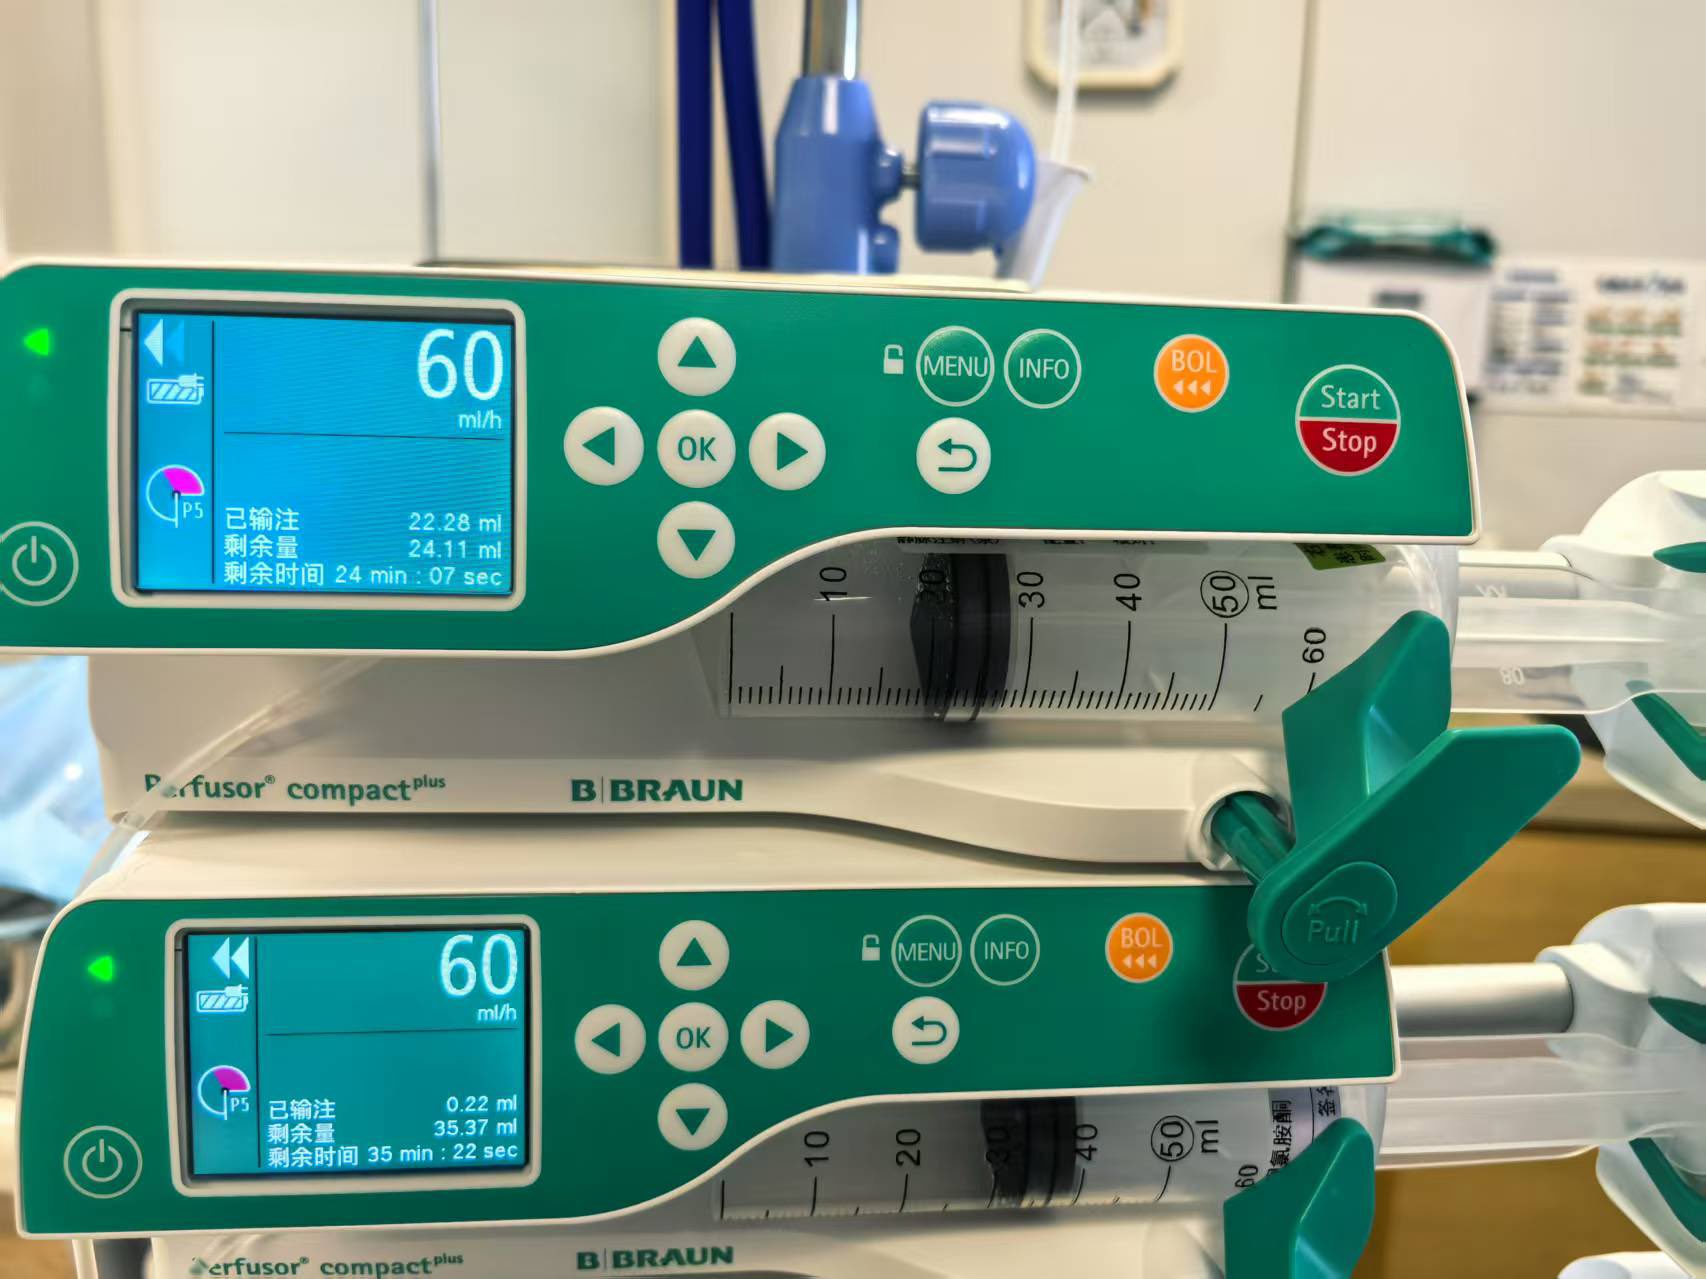

真的会推荐发作的时候或难治性抑郁做氯胺酮🥺关于价格,不算私立医院或住院的情况,一般一次是800...其实以前药费也有吃到过很高

不会像mect那样副作用很可怕,我的感觉是几乎没有负面影响

顺着这个思路用的auv对我效果也很好。那么漫长的寻找和尝试总算有了相对稳定的解法..太好了